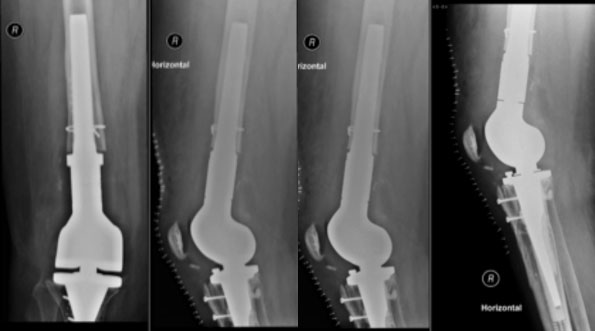

Postoperatives Röntgenbild nach Wechsel der gelockerten Knieprothese